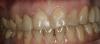

ZHAR Опубликовано 1 сентября, 2012 Поделиться Опубликовано 1 сентября, 2012 Пациентку направил коллега на удаление 12 зуба.Отсутствие феррула, постоянные расцементировки.2 часа времени.удаление люксатором, альфа-био 16Х3.3, торк 40+, в щели альфа-графт, пластиковый абатмант, коронка из композита смоделированная во рту и в руках. Ссылка на комментарий

kriokov Опубликовано 1 сентября, 2012 Поделиться Опубликовано 1 сентября, 2012 топикстартеруспасибо за кейс, понравился выбор метода леченияна фотке с коронкой кажется , что она как бы широковатая в пришеечной области, сосочек к 12 чуть уплощени шовник толстоват Ссылка на комментарий

Orient Опубликовано 1 сентября, 2012 Поделиться Опубликовано 1 сентября, 2012 дистальній контакт 11го бі подкорретировал ,если хотите номармальній сосочек! Ссылка на комментарий